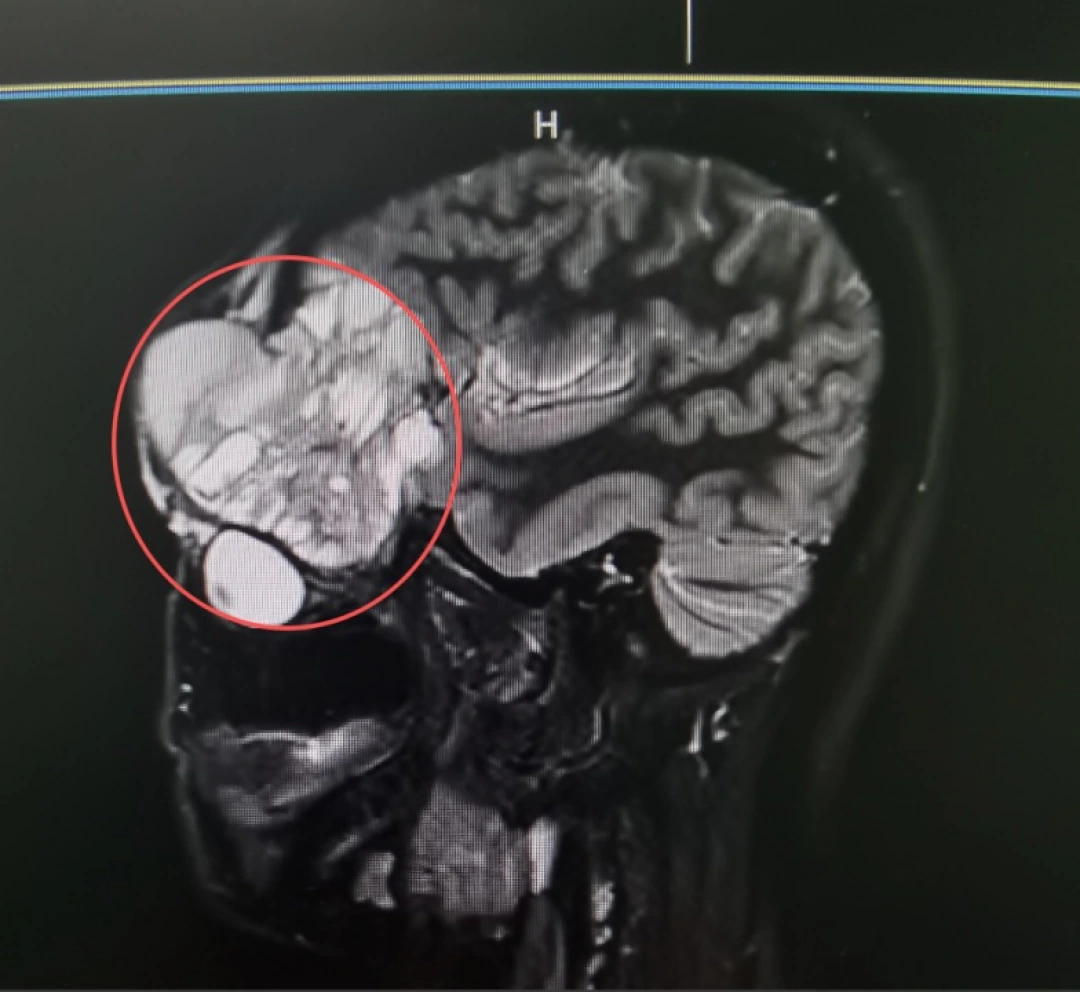

近日,陈女士因肿瘤多次术后复发,左眼眶肿胀2月余,来到湖南中医药大学第一附属医院就诊。入院时影像检查显示:肿瘤沿上颌骨向上浸润性生长,侵犯至眼眶,推挤眼球并累及眶尖重要结构,进一步攀升至颅底,紧贴守护大脑的“最后屏障”——硬脑膜。

治疗时,既要完整切除肿瘤,降低复发风险;又要最大限度保留面部外观与眼球、神经等重要结构。手术需在视觉神经与大脑交界处进行毫米级操作,稍有不慎,就可能引发严重并发症,治疗难度极大。

由医院耳鼻咽喉头颈外科主任胡革、副主任医师吴文科,神经外科副主任医师余文运等医护人员组成手术团队,在显微镜下精准分离肿瘤边界,保护眼眶、视神经及颅底重要血管神经;并完整切除了侵犯颅底、眶上及颅内的肿瘤组织,并第一时间将眼球复位,对眶壁与颅底进行重建与修补。